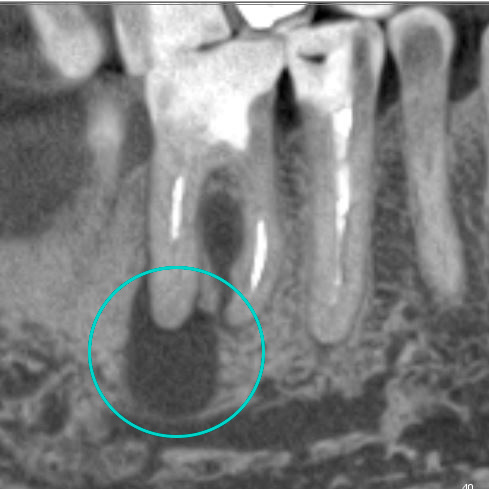

“Киста зуба” – это упрощенное название хронического периодонтита, которая образуется в результате воспаления. Ранее “кисты” часто становились причиной удаления зуба. Сегодня, благодаря современным методам, периодонтит можно лечить, сохраняя зуб. Выбор метода лечения зависит от размера и расположения “кисты”, а также от общего состояния зуба.

— Удалить “кисты” без повреждения зуба

— Вылечить апикальный периодонтит (воспаление на верхушке корней или за верхушкой корней, может возникать вследствие осложненного кариеса)

— Перелечить каналы зубов заново